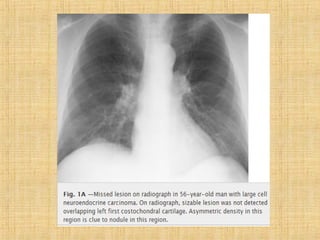

As principais informações do documento são: 1. Discute os padrões de doença pulmonar causados por metástases, incluindo nódulos, espessamento intersticial e obstrução das vias aéreas. 2. A prevalência de metástases pulmonares varia de 30-55% dependendo do tumor primário, e são mais comuns em pacientes acima de 50 anos. 3. Os achados clínicos mais comuns são dispneia, hemoptise e febre, enquanto exames de escarro ou lavado brô